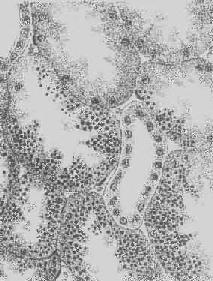

图1-18 肝细胞脂肪变性 肝细胞胞浆内出现大小不等的脂肪空泡;右上角为饿酸染色的脂肪细胞, 脂滴染成黑色 (2)心肌脂肪变性:心肌在正常情况下可含有少数脂滴,脂肪变性时脂滴明显增多。镜下,脂肪空泡较细小,呈串珠状成排排列,主要位于肌纤维Z带附近和线粒体分布区。常为贫血和中毒的结果。在严重贫血时,可见心膜下尤其是乳头肌处出现成排的黄色条纹,与正常心肌的暗红色相间排列,状若虎皮斑纹,故有“虎斑心”之称。严重感染、白喉外毒素以及其他毒物(如磷、砷、氯仿等)也能引起心肌的弥漫性脂肪变。肉眼观,心肌均匀变浊,略呈黄白色。但通常心功能并不受明显影响。显著的心肌脂肪变性如今并不常见。 (3)肾脂肪变性;在严重贫血、缺氧和中毒过程中,或肾小球毛细血管通透性升高时,肾小管特别是近曲小管的上皮细胞可吸收漏出的脂蛋白而导致脂肪变性。脂滴起初多位于细胞基底部。肉眼观,肾稍肿大,切面上可见皮质增厚,略呈浅黄色。 2.玻璃样变性 又称透明变性(hyaline degeneration),为十分常见的变性,主要见于结缔组织、血管壁,有时也可见于细胞内。 1.结缔组织玻璃样变:常见于纤维瘢痕组织、纤维化的肾小球,以及动脉粥样硬化的纤维性瘢块等。此时纤维细胞明显变少,胶原纤维增粗并互相融合成为梁状、带状或片状的半透明均质,失去纤维性结构(图1-19)。质地坚韧,缺乏弹性。玻璃样变的发生机制尚不甚清楚,有人认为在纤维瘢痕老化过程中,原胶原蛋白分子的交联增多,胶原原纤维也互相融合,其间并有较多的糖蛋白积聚,形成所谓玻璃样物质;也有人认为可能由于缺氧、炎症等原因,造成局部pH升高或温度升高,致使原胶原蛋白分子变性成明胶并互相融合所致。 2.血管壁玻璃样变:这种改变常见于高血压病时的肾、脑、脾及视网膜的细动脉。此时,可能是由于细动脉的持续性痉挛,使内膜通透性增高,血浆蛋白得以渗入内膜,在内皮细胞下凝固成无结构的均匀红染物质。此外,内膜下的基底膜样物质增多。这些改变使细动脉的管壁增厚、变硬,管腔变狭,甚至闭塞(图1-20),此即细动脉硬化症(arteri-olosclerosis),可引起肾及脑的缺血。 3.细胞内玻璃样变:亦称为细胞内玻璃样小滴变性。这种情况常见于肾小球肾炎或其他疾病而伴有明显蛋白尿时。此时肾近曲小管上皮细胞胞浆内可出现许多大小不等的圆形红染小滴(图1-21),这是血浆蛋白经肾小球滤出而又被肾小管上皮细胞吞饮的结果,并在胞浆内融合成玻璃样小滴,以后可被溶酶体所消化。此外,在酒精中毒时,肝细胞核周胞浆内亦可出现不甚规则的红染玻璃样物质。电镜下,这种物质由密集的细丝构成,据认为可能是细胞骨架中含角蛋白成分改变的结果,并被称为Mallory小体。